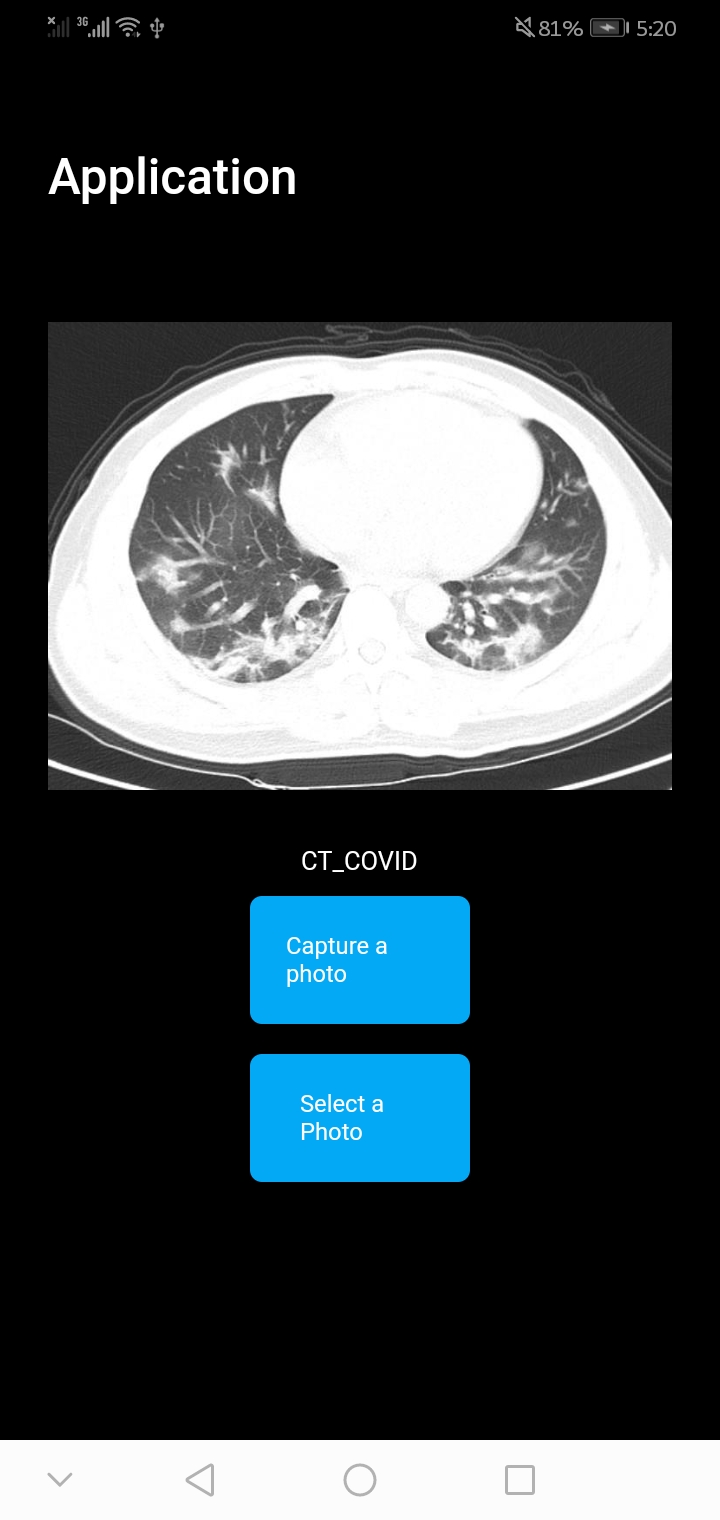

After this step, we have a label file and a model with metadata. Specify appropriate application development (Section, 2.6) used flutter image classification template. Examples of the final application at work can be seen in Figures 7(a) and 7(b).

In execution and final considerations (Step 7, section 2.7), we considered the first 5 images from both (CT_COVID and CT_nonCOVID) categories for the final testing on mobile phone, and those images were not part of model training/testing. We tested the model performance on the mobile phone in real-time, and the final accuracy was 0.6, which means the model cannot be deployed, but the performance increased to 0.80 percent when images were loaded from the gallery (Flutter App).